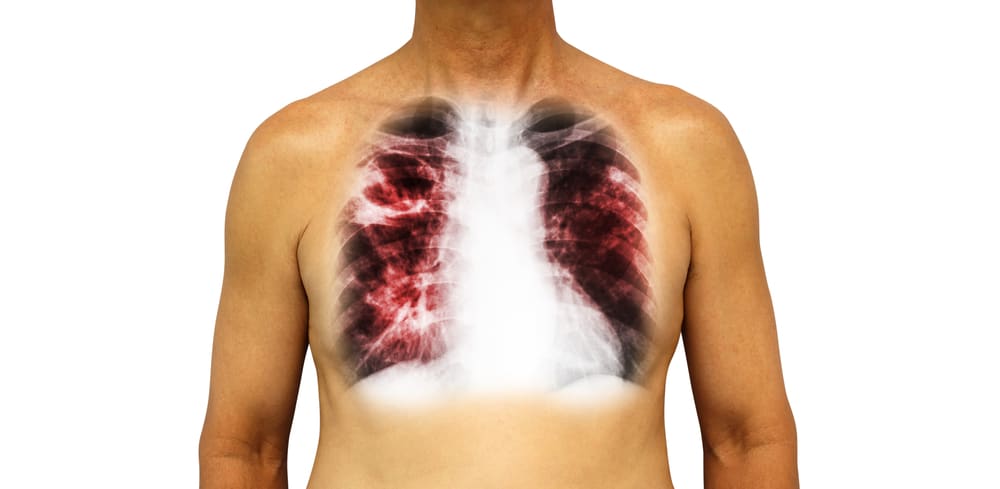

फेफड़े की टीबी या पल्मनरी टीबी (Pulmonary Tuberculosis) जिसे श्वास संबंधी टीबी भी कहा जाता है, प्रमुख रूप से हमारे फेफड़ों को प्रभावित करती है। इस तरह की टीबी फेफड़े से किसी अन्य अंग में भी फैल सकती है। यह एक बैक्टीरियल इंफेक्शन माइकोबैक्टीरियम ट्यूबरकुलोसिस नामक बैक्टीरिया के कारण होता है जो लोगों के बीच हवा के माध्यम से फैलता है। जब यह फेफड़ों को प्रभावित करता है, तो इसके कारण फेफड़े की टीबी हो सकती है। फेफड़े की टीबी होने पर सीने में दर्द, गंभीर खांसी जैसे और अन्य लक्षणों की स्थितियां होने लगती है।

टीबी के बैक्टीरिया मुख्य रूप से फेफड़ों में ही पनपते हैं, लेकिन वे शरीर के अन्य हिस्सों को भी संक्रमित कर सकते हैं। अपने इस आर्टिकल में हम आपको फेफड़े की टीबी के लक्षण, कारण और उपचार के बारे में जुड़ी जरूरी बातें बताएंगे।